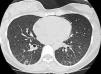

A la exploración física la paciente se encontraba afebril, taquicárdica (140latidos/min), taquipneica (36respiraciones/min) y con una saturación basal de oxígeno (respirando aire ambiente) del 91%. La auscultación pulmonar mostraba un murmullo vesicular conservado con crepitantes bibasales. En la analítica sanguínea destacaba un ionograma normal, proteína C reativa 80g/dl, leucocitos 11.430/mm3 (90% de neutrófilos y 1,4% de eosinófilos), hemoglobina 12,4g/dl, hematocrito 36,4%, plaquetas 309.000mm3. Gasometría arterial basal con pH7,44, pCO2 31mmHg, pO2 54mmHg, CO3H 21,1mmol/l. La radiografía de tórax muestró un patrón micronodular bilateral de predominio bibasal asociado a discreto engrosamiento cisural. Se realiza fibrobroncoscopia diagnóstica, en la que no se observan lesiones endobronquiales, y se recogen muestras del lavado y aspirado bronquioloalveolar, además de una biopsia transbronquial. En el lavado se observan linfocitos en cantidad moderada y algunos polimorfonucleares. No se observan eosinófilos. La biopsia mostró fragmentos de parénquima pulmonar con aislados de granulomas epitelioides, no necrosantes y con células gigantes aisladas, situados a nivel septal. Las tinciones histoquímicas para detección de bacilos ácido-alcohol resistentes (Kin-Youn) fueron negativas. También el broncoaspirado resultó negativo para malignidad. En 3 muestras de cultivos de esputo se aisló Mycobacterium avium, y el estudio de precipitinas para palomas fue negativo. La tomografía de tórax (TACAR) mostró un patrón intersticial con nódulos centrolobulares bilaterales y difuso, junto con imágenes de consolidación de la vía aérea en partes declives de ambas bases en probable relación con atelectasia, así como neumomediastino con relación a biopsia transbronquial. No se apreciaban adenopatías patológicas mediastínicas ni axiales (fig. 1).